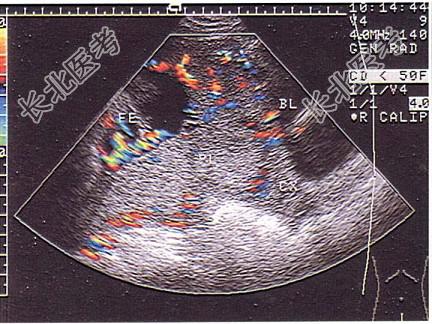

- 单项选择题女性,25岁, 停经33周。阴道无痛性出血2天。B超检查如图,以下最可能的诊断为 ( )

A、中央性前置胎盘

E、边缘性前置胎盘